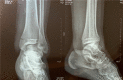

Case summary: A 16-year-old patient sustained left medial malleolar fracture, and the associated inferior tibiofibular syndesmotic instability was overlooked. After open reduction and internal fixation of the medial malleolar fracture, inferior tibiofibular syndesmosis diastasis with IOM rupture was detected by auxiliary imaging. Secondary surgical intervention was performed to reduce anatomically and fix with two trans-syndesmosis screws. Twelve weeks later, the screws were removed. At the 6-mo follow-up, the patient gained full range of motion of the ankle.